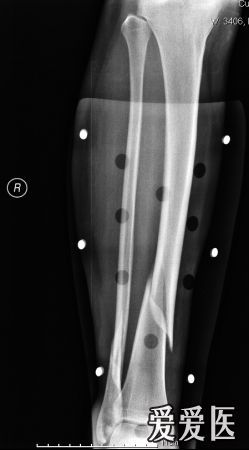

我是六月十八号摔着的,胫骨远端螺旋形骨折,下图是九月三号拍的片子

小腿中下段螺旋形骨折髓内针固定,锁钉安装后发现有旋转移位

右胫骨螺旋形骨折,2.右腓骨下段